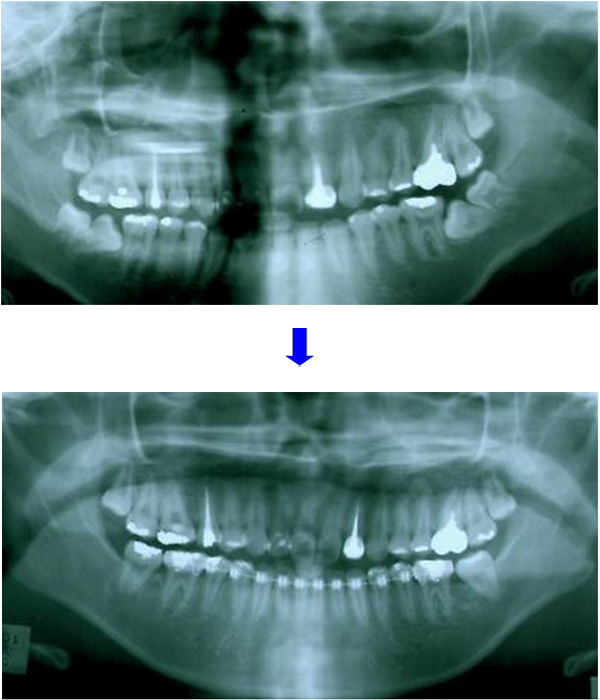

dot  扶正大臼齒

案例